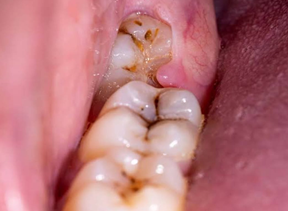

Dental caries

Tooth fully arrested by caries and tooth become un restorable.

દાંત નો સડો

જ્યારે આખો દાંત સડી ગયો હોય અને બચાવી શકાય એવું ન હોય ત્યારે દાંત કાઢવો પડે છે.

3rd Molar

In some case 3rd molar was causing discomfort, pain or damaging tooth nearby, must be extracted.

ડાહપણ દાઢ

ડાહપણ દાઢ દુ : ખાવો કરતી હોય અથવા બાજુના દાંતને નુકસાન પહોંચાડતી હોય